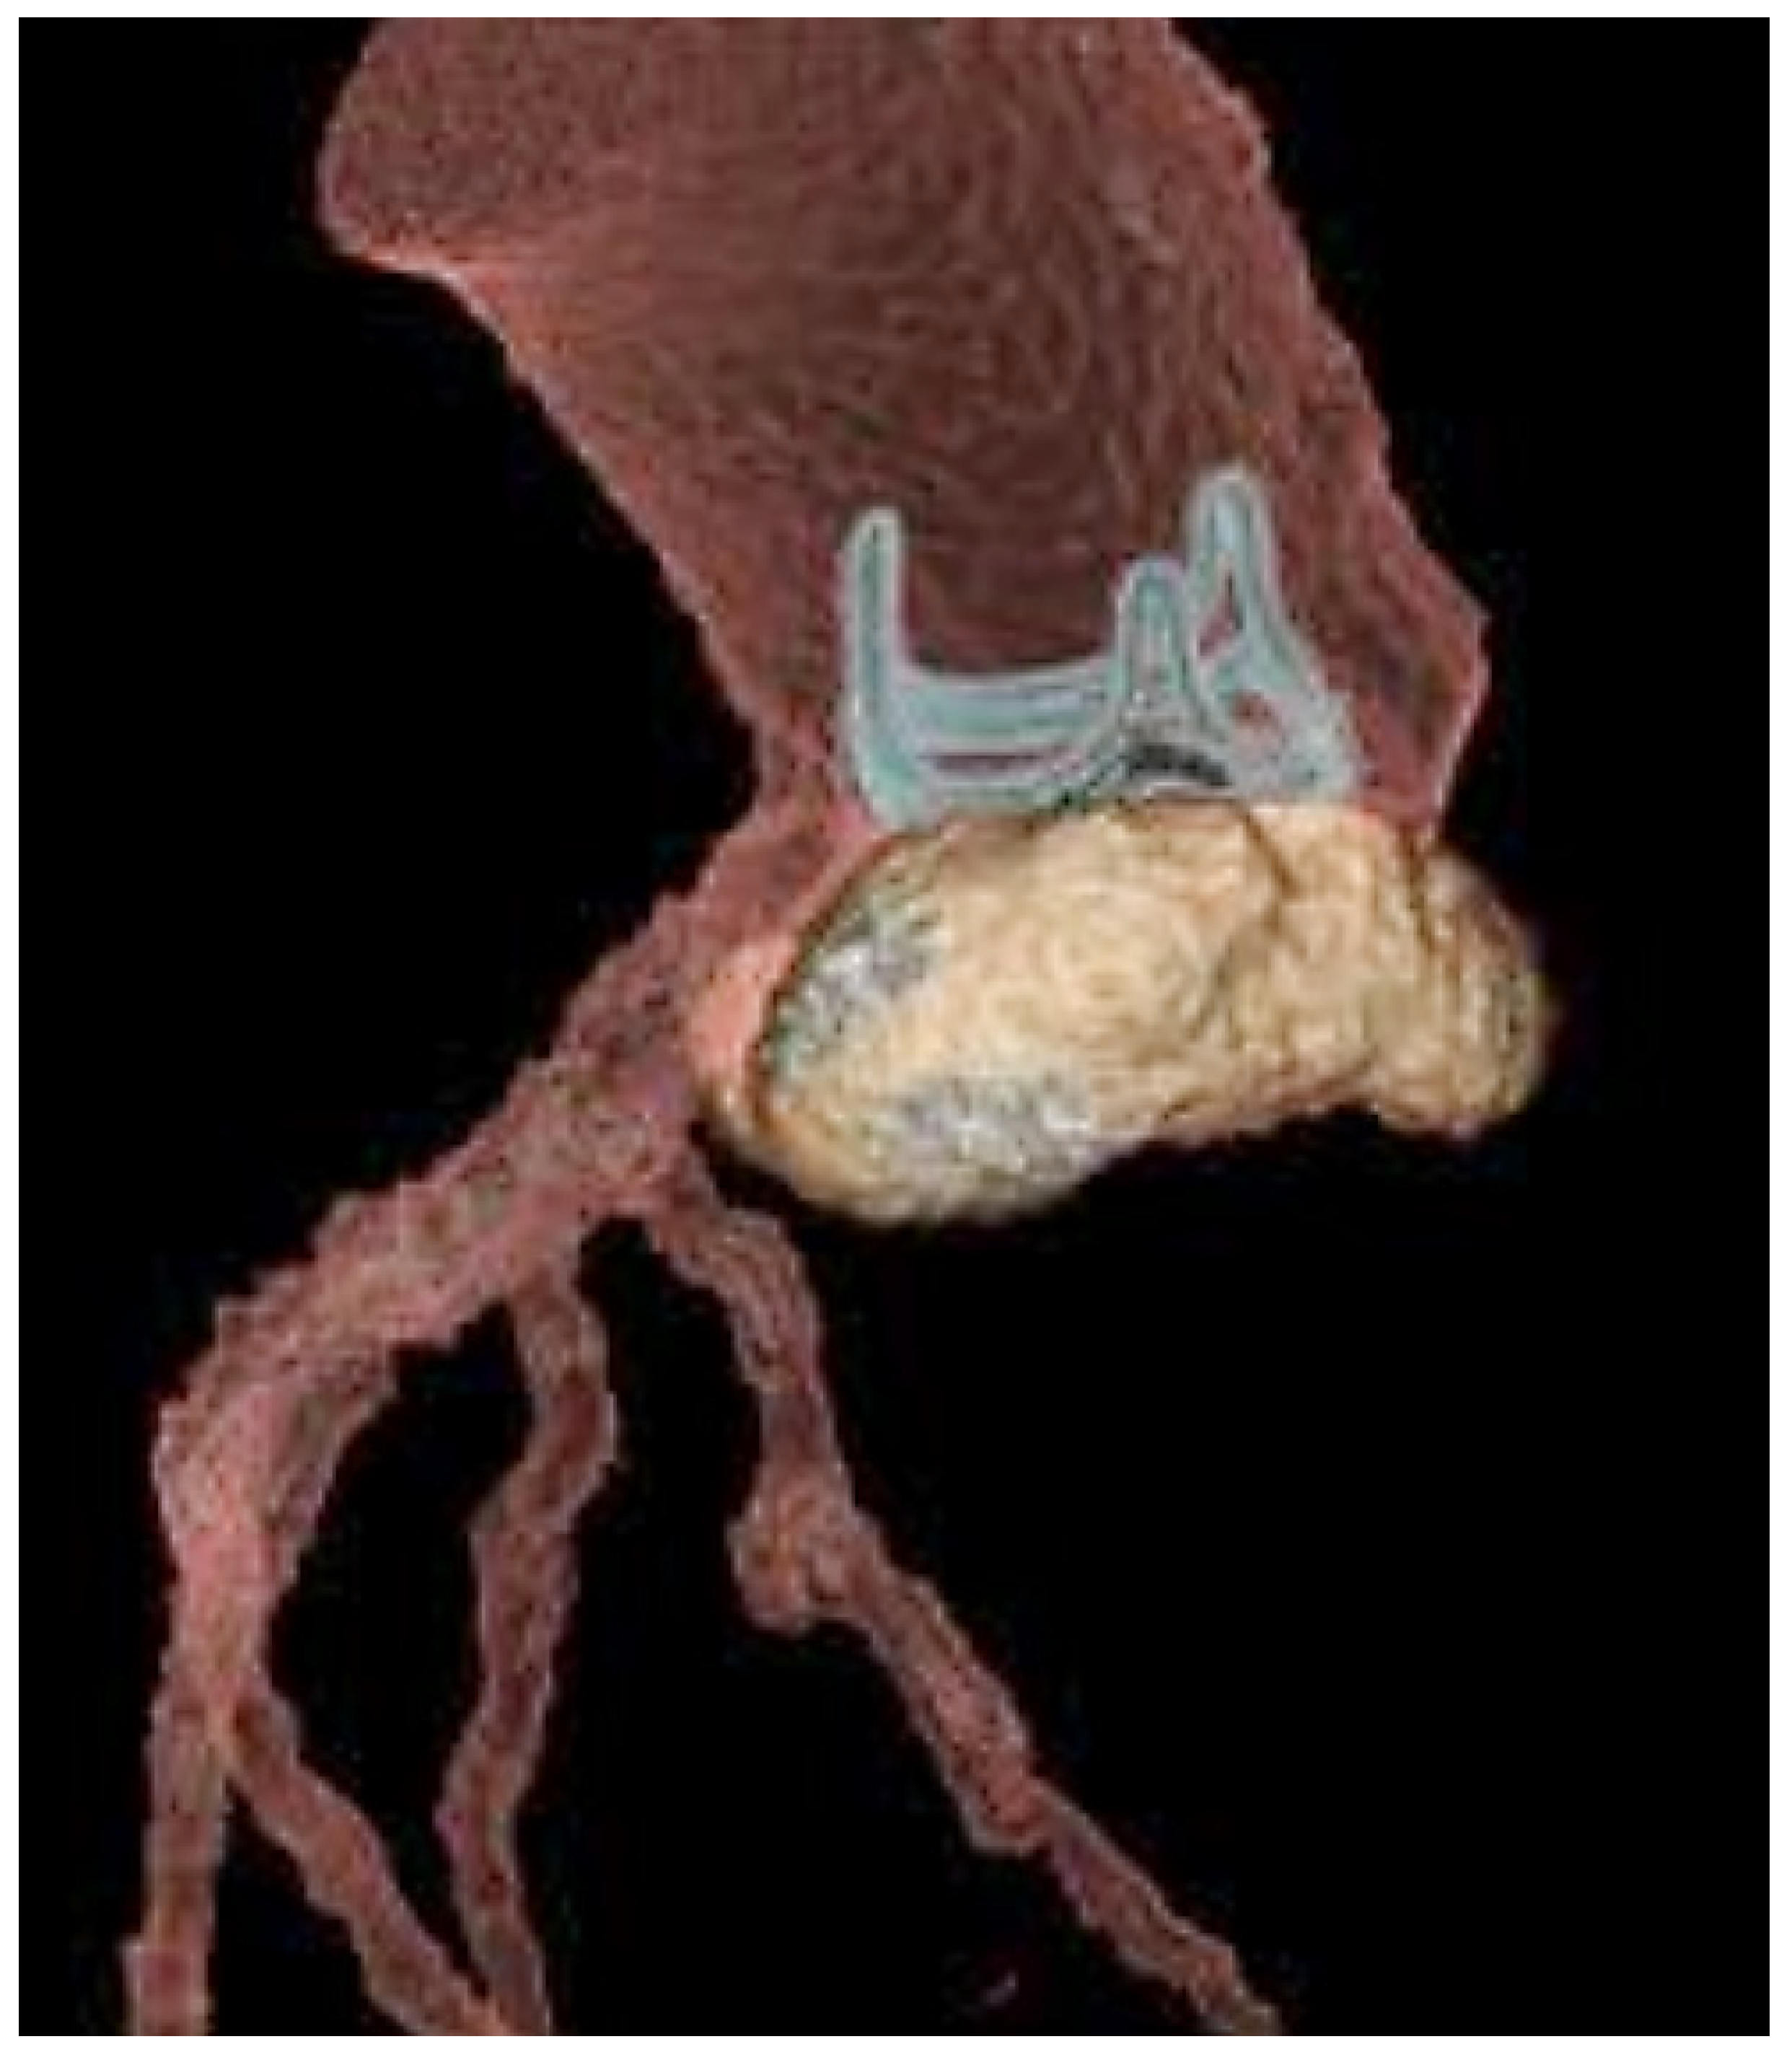

- Khalique, O.K.; Veillet-Chowdhury, M.; Choi, A.D.; Feuchtner, G.; Lopez-Mattei, J. Cardiac computed tomography in the contemporary evaluation of infective endocarditis. J. Cardiovasc. Comput. Tomogr. 2021, 15, 304–312. [Google Scholar] [CrossRef]

- Oliveira, M.; Guittet, L.; Hamon, M.; Hamon, M. Comparative value of cardiac CT and transesophageal echocardiography in infective endocarditis: A systematic review and meta-analysis. Radiol. Cardiothorac. Imaging 2020, 2, e190189. [Google Scholar] [CrossRef]